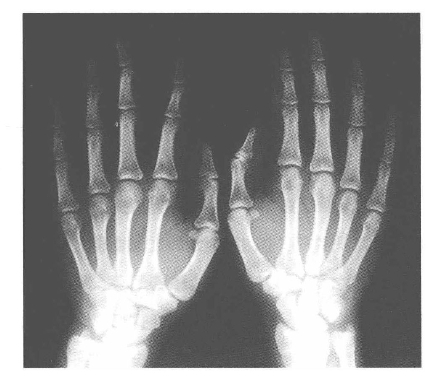

更有意思的是,当他手执小铅板放到阴极射线管前面时,在亚铂氰化钡屏上出现的不但有铅板的轮廓,竟然还有他手指浅浅的阴影,最奇的是,他竟然在手指的阴影里看到了其骨骼清晰的轮廓。(https://www.daowen.com)

这天晚上,刚好他夫人来了,他立即游说夫人接受他神奇的实验,夫人便将手伸到了阴极射线管前。一刻钟之后,她将手挪开了,她看到了一张照相底片,上面有一只张开五指的手,肉已经被剥掉了,只剩下骨头!

这就是世界上第一张X光片。这年12月,伦琴写出了著作《一种新射线》,文中详细地介绍了他发现的这种神秘的射线。

X射线下的手